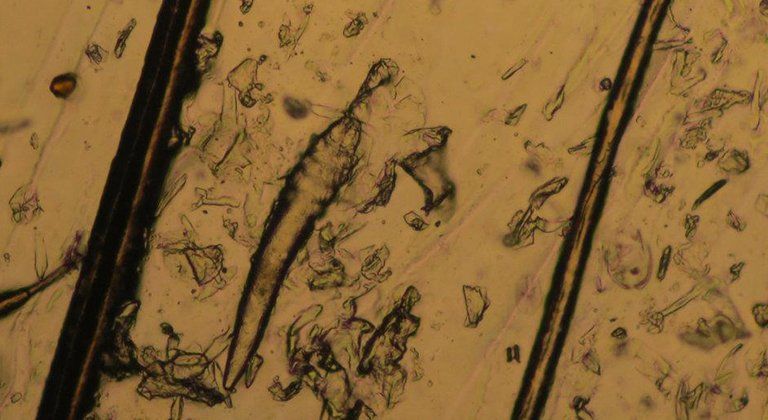

Medicina di laboratorio